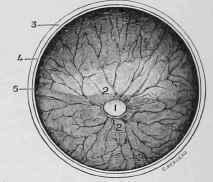

Fig. 248. - Fundus of the Eye.

1, Entrance of the Optic Nerve to form the Retina. 2, 2, Blood-vessels entering around it (there is no arteria centralis retinae in the horse as in man). 3, Divided Sclerotic. 4, Divided Choroid. 5, Divided Retina.

Having the eye in a good light, the examiner will note the white portion of the globe, with its numerous vessels ramifying in all directions, and the transparent cornea forming the front of the eye. Looking through the cornea he will observe the curtain behind it which gives the colour to the eye, and is therefore termed the iris, with the opening in the centre of it, the pupil, through which the light passes, carrying with it the image which is to be depicted on the retina. At the edge of the pupilary opening the small black, pea-like bodies, which have been described as the corpora nigra, will be seen; small, or even extremely minute, at the lower edge of the pupil, considerably larger at the upper edge, these little bodies are worth particular attention, because they are constantly taken by the inexperienced for a diseased condition of the eye. Looking through the pupilary opening, if the eye is in the proper position, the examiner will see a small pearl-like body at the bottom of the posterior chamber which marks the entrance of the optic nerve (fig. 248, l); this body is worthy of particular notice as it is frequently mistaken for a cataract.